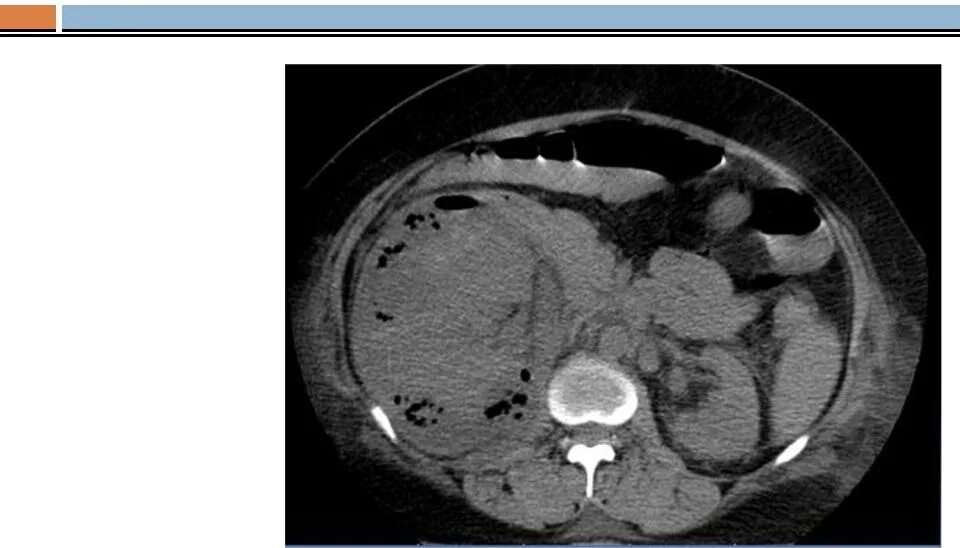

Пиелонефрит кт